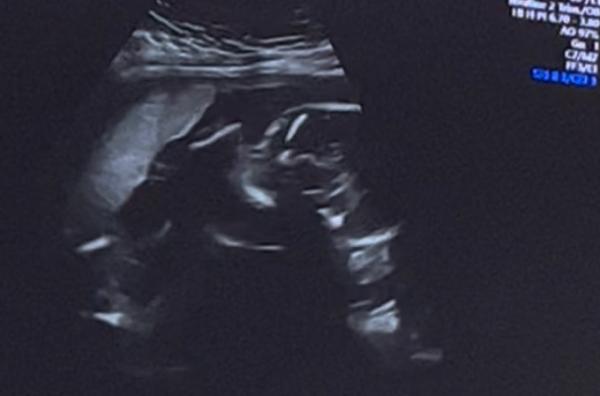

Soweit alles supi, Baby hat geschlafen. 400 Gramm 22cm groß und alles dran was dran sein muss. Seitenwandplazenta, Gebärmutterhals bei 4cm. Alles supi Dupi.